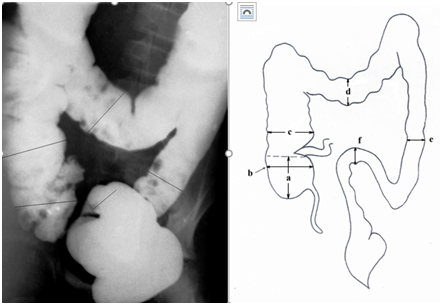

Figure 2 Lateral x-ray image of the anorectal zone of a child of 13 years and its schematic representation.

The axis of the anal canal (AC) is displaced anteriorly from the axis of the vertical branch of the rectum (OK). NM – axis of the horizontal branch of the rectum; PRM – puborectalis muscle, P – pubis, R – radiopaque marker is located near the anus. Its true diameter is 1.6 cm. The distance between the rectum and the marker lying along the posterior contour of the tip is the length of the closed anal canal. The black line is the place of measurement of the width of the rectum .

The distance between the marker (anus) and the rectum, which does not contain a contrast agent is equal to the anal canal length measured by the manometric method. This is a zone of the anal canal contraction. The table shows the results of measuring the width of the rectum, all parts of the colon, as well as the length of the anal canal, the height of the dome of the cecum and the volume of the colon in milliliters of barium injected (Table 1).